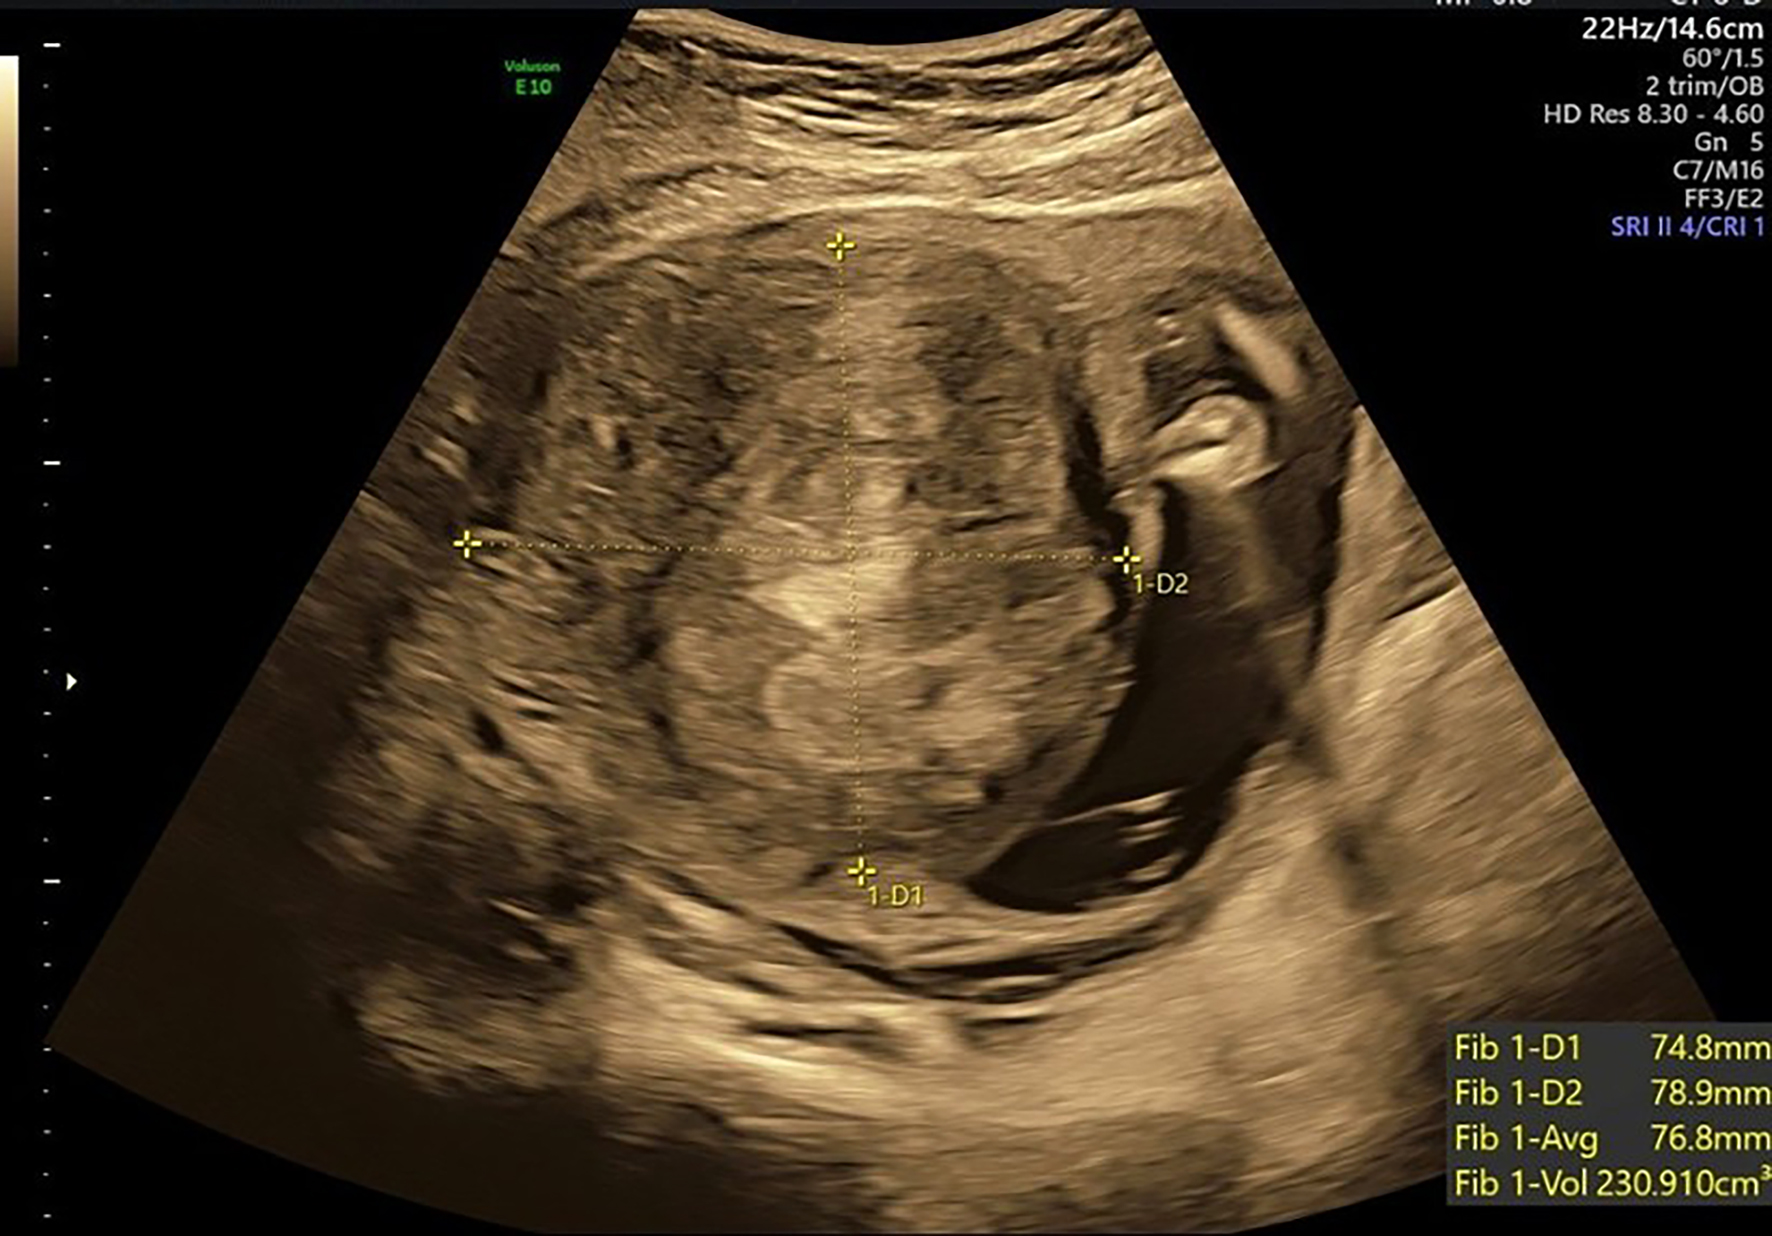

A 35-year-old primigravida with gestational diabetes mellitus, managed with dietary modification and good glycemic control, presented at 38 + 2 weeks’ gestation with fetal growth restriction (FGR). At 20 weeks’ gestation, ultrasound examination revealed a large anterior intramural fibroid in the lower segment, measuring 7.5 × 7.9 cm (Fig. 1). At 38 weeks’ gestation, ultrasound assessment demonstrated an estimated fetal weight of 2,374 g (below the 10th percentile) with normal umbilical artery findings. The fibroid measured 5.9 × 7.6 cm in the right lower uterine segment; the apparent reduction in dimensions likely reflected measurement artifact attributable to restricted acoustic windows at late gestation, rather than true fibroid regression.

Figure 1. Prenatal ultrasound at 20 weeks’ gestation showing an anterior-wall intramural fibroid (yellow cross-marks) measuring approximately 7.5 × 7.9 cm. The lesion was in the lower anterior uterine segment.